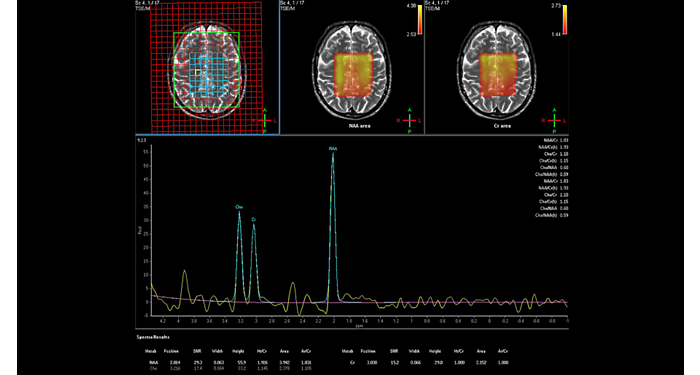

70% of radiologists consider neuro indications to be challenging, mostly due to a lack of appropriate imaging and visualization techniques¹. Philips aims to provide the best possible diagnostic clarity and treatment guidance for all patients with neurological disorders. By leveraging our dStream digital platform, this year, we are introducing, a set of novel imaging and visualization strategies. These may empower you to resolve complex neuro questions with more certainty, as well as unlock new neuro territories in advanced Neurofunctional applications. This is a key step towards elevating neuro diagnostics and ultimately touching more lives with MR imaging. ¹ TMTG Market Survey 2016

New neuro applications